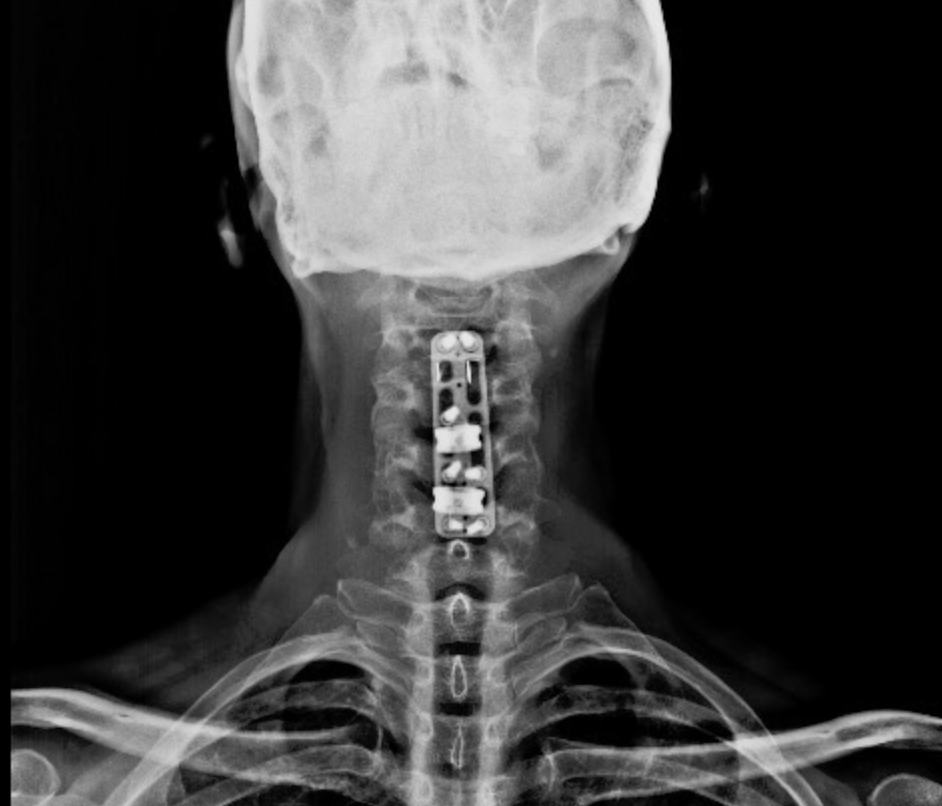

RESULTADOS